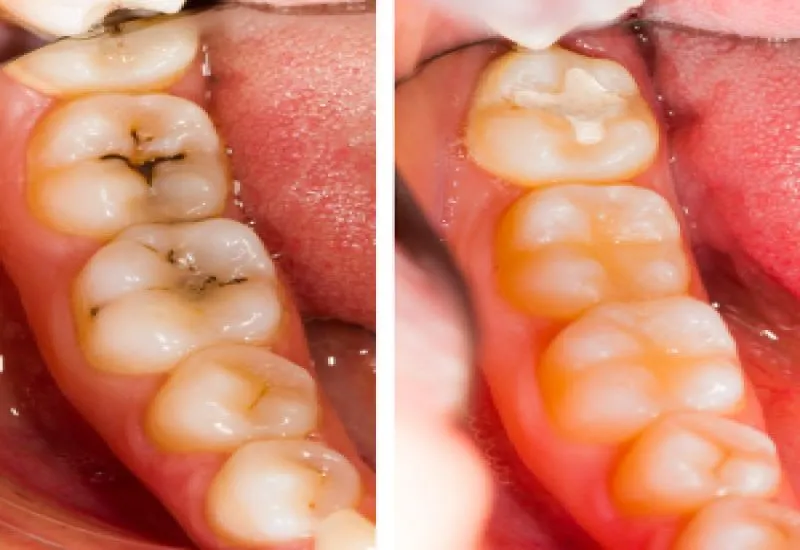

Galeria zdjęć: od plamy próchnicowej po zaawansowany ubytek

Dokładne przyjrzenie się zdjęciom przedstawiającym różne etapy próchnicy od niewinnej, białej plamki na szkliwie, przez ciemniejący punkt w bruździe, aż po widoczną, głęboką dziurę jest niezwykle pomocne. Wizualizacje te pozwalają na lepsze zrozumienie, jak choroba postępuje i jak zmienia wygląd zdrowego zęba. Dzięki nim możesz nauczyć się rozpoznawać potencjalne problemy we własnej jamie ustnej.

Czym różni się zdrowa bruzda od bruzdy z próchnicą? Porównanie

Zdrowa bruzda na powierzchni żującej zęba jest gładka, jednolita w kolorze i nie wykazuje żadnych przebarwień ani zagłębień. Natomiast bruzda dotknięta próchnicą często wygląda inaczej: można zauważyć w niej ciemne punkty lub linie, które wskazują na początek ubytku. Szkliwo w tym miejscu może być matowe, a sama bruzda może wydawać się głębsza lub mieć nieregularny kształt z powodu postępującej demineralizacji i destrukcji tkanki.